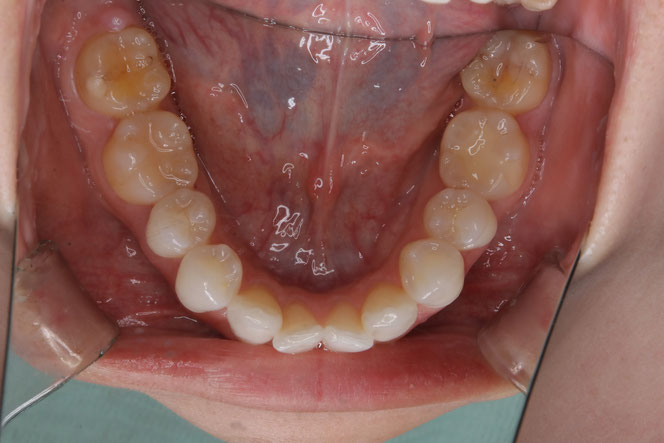

治療後の変化

再生治療により、

2~3ミリ下がっていた歯ぐきが回復。

歯の長さが自然なバランスに戻り、

厚みのある丈夫な歯ぐきが再建されました。